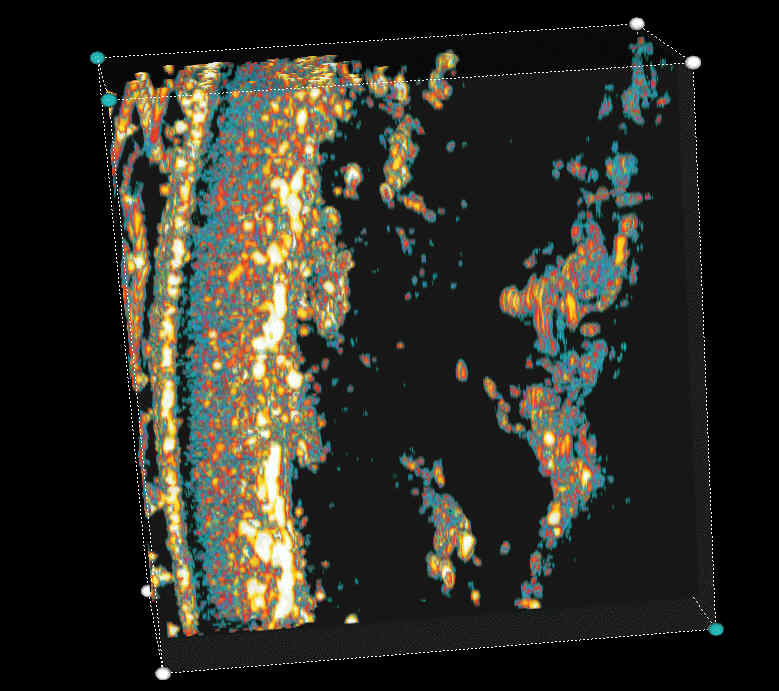

20 MHz 3D images

| Misc. |  Cellulite, arm |

Microdialysis tube |

Intradermal nevus |

Highlight. intrad. nevus |

| Misc. |  Ageband, forearm |

Nevus, skin parallel cut |

Normal, overlying hairs |